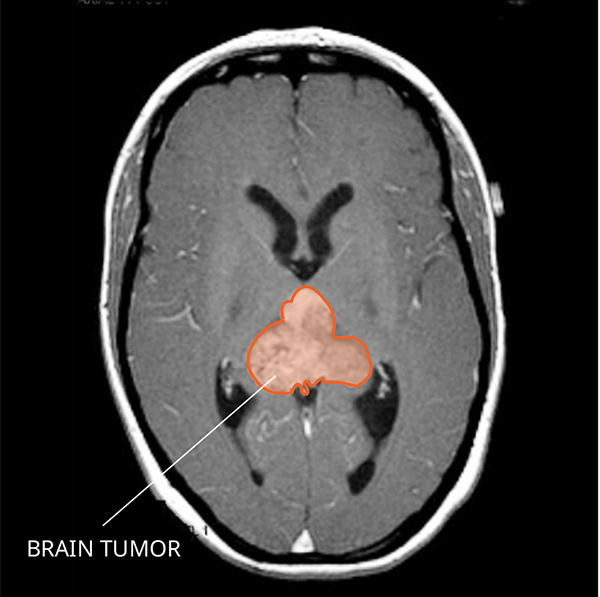

What Do AT/RTs Look like on an MRI?

AT/RTs usually appear very large with fluid-filled areas that often brighten with contrast on a magnetic resonance imaging (MRI) scan. You can often see areas of bleeding or dead tissue.